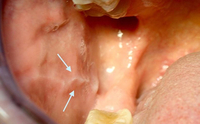

A linha alba (linha branca) é uma hiperqueratose da mucosa bucal nas bochechas, representando uma impressão dentária na face interna da bochecha

Da coleção da Profa. Daniele Manfredini